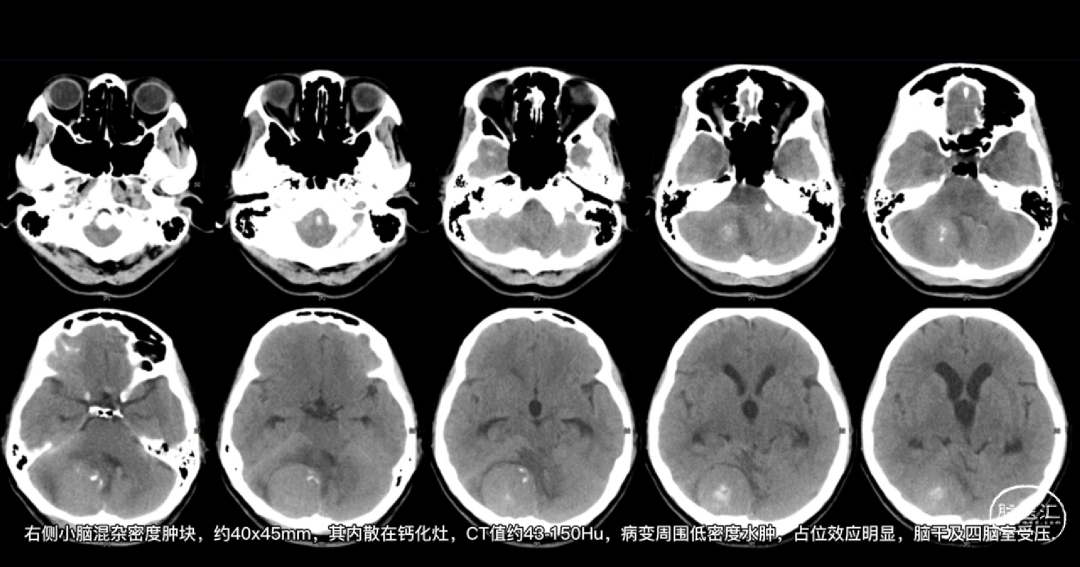

患者王**,52岁,女性。

患者以“头痛、头晕伴行走不稳半年,加重2天”入院。

入院查体:体温36.5℃;脉搏77次/分;血压140/76mmHg,神志清楚,精神差,查体合作,双侧瞳孔等大等圆,直径约2.5mm,对光反射敏捷,伸舌偏右,指鼻试验、轮替试验+,四肢肌力、肌张力正常,生理反射存在,病理征阴性,小脑征阳性。